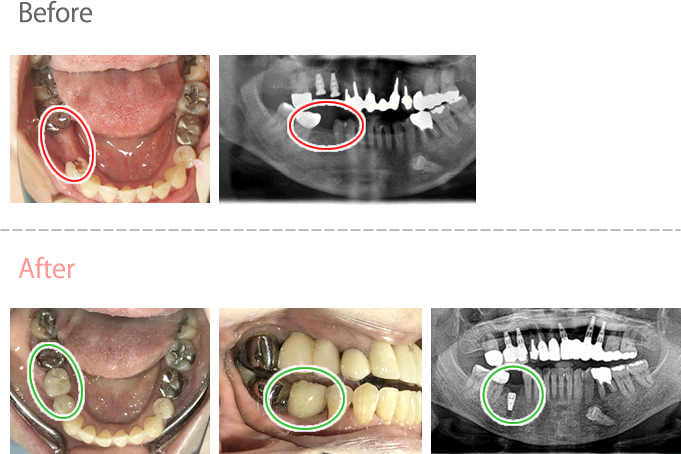

女性Kさん 50代(インプラント)

左下の抜けているところに歯を入れたい。

治療内容

インプラントを2本埋入しました。

所感

以前、1本歯がないところを、欠損の両側に被せ物をしてつないだブリッジでした。その2本のうちの前方の歯が歯根の破折を起こし、抜歯になり2本の欠損になりました。この2本の欠損を補う方法には、部分入れ歯、再度ブリッジ、インプラントの3つの方法があります。部分入れ歯もブリッジも欠損部分の負担をほかの歯に負わせるため、支台になった歯は負担が大きくなり、虫歯、歯周病、歯根破折の危険性が高まり、さらに歯を失うことになります。インプラントは、それ自身が単体で植立しているため他の歯に負担を負わすことがありませんので、咬合を回復させるだけではなく、他の歯を守る役割もあります。今回もX-Guideを使った埋入で、安心安全に行うことできました。

インプラント2本:¥363,000×2本=¥726,000(税込)

Before

After